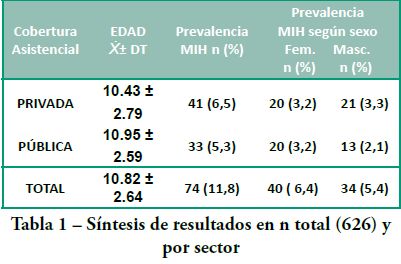

Se evaluaron 626 niños (163 en el sector privado y 463 en la Facultad de Odontología) con una edad promedio de 10.82 ± 2.64. El valor de la prevalencia de MIH total fue de 11,82% (9.3-14.3).

En la tabla 1 se sintetizan los resultados de: prevalencia de MIH por tipo de cobertura, rangos etarios, media, desvío típico y distribución por sexo.

Prevalencia MIH según lugar de asistencia

Grupo 1 Sector Privado:

n=163 niños (41 se diagnosticaron con MIH),

Edad promedio 10.43 ± 2.79

La prevalencia de MIH fue de 25.2%. (Gráfica 1)

Grupo 2 Secor Público:

n=463 (33 se diagnosticaron con MIH)

Edad promedio 10.95 ± 2.59

La prevalencia de MIH fue de 7.13%. (Gráfica 2)

Distribución MIH según género

Grupo 1 Sector Privado (Gráfica 3):

masculino (21) 51.2%

femenino (20) 48.8%

Grupo 2 Sector Público (Gráfica 4):

masculino (13) 39.4%

femenino (20) 60.6%.

En este estudio los resultados muestran una prevalencia de MIH de 11,8% y se obtuvo una alta correlación significativa entre MIH y el año de nacimiento (p<0.0001).

Los resultados permiten confirmar que: 1) MIH es una patología frecuente en la muestra estudiada de la ciudad de Montevideo, Uruguay, 2) que los pacientes con mejor acceso al cuidado de su salud presentan mayor prevalencia de MIH. 3) No se encontraron diferencias significativas al comparar la distribución por sexo ni en relación a a las piezas dentarias afectadas 4) Se encontró una correlación positiva y altamente significativa en relación al año de nacimiento. 5) La relevancia de MIH como patología emergente hace necesario investigaciones con muestras poblaciones mayores y de alcance nacional 6) nuevos estudios pudieran diseñarse en base a la hipótesis que relaciona MIH con el status socioeconómico.